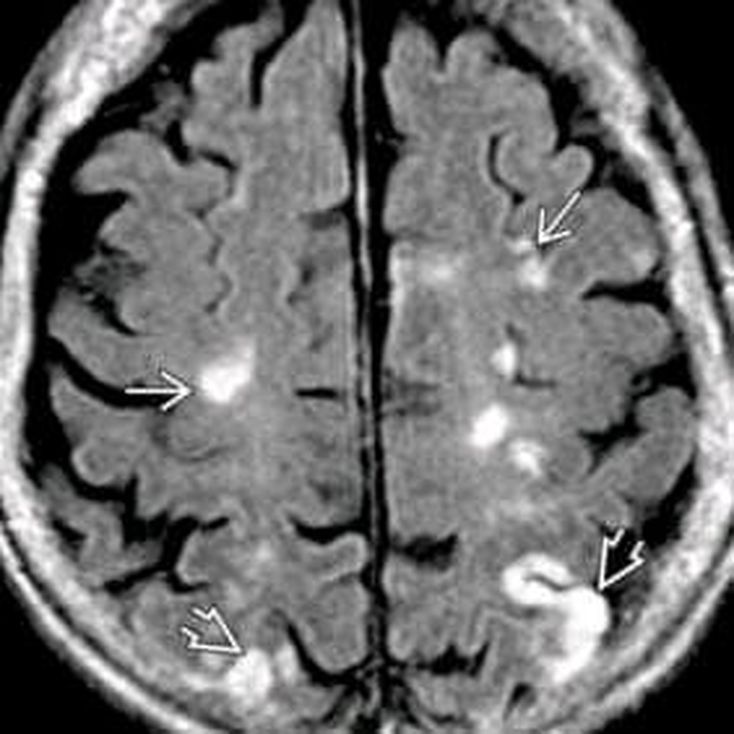

What is your diagnosis?

MS

Multiple sclerosis

Infarct of brain

Ischemic infarction.

calcification